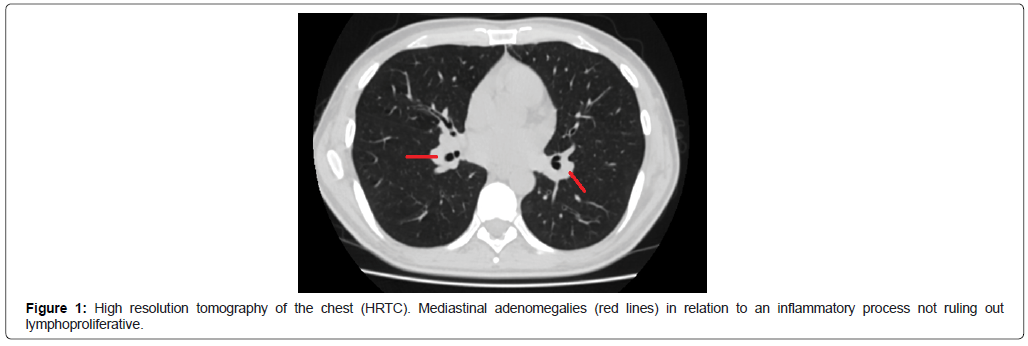

A man, 39 years of age, single, without profession, alcoholic, single, man who has sex with men (MSM), seroconcordant couple who died of AIDS. He consulted the institution for a clinical picture of 1 month of evolution consisting of subjective, intermittent fever that appears at intervals of 3 to 5 days, associated with chills, asthenia, adynamia and intermittent diarrhea without blood, plus 1 month of onset of cervical and inguinal adenopathies (not susceptible to biopsy), not painful, due to which he consulted at the first level of attention, where they perform studies including presumptive HIV test which is positive and is confirmed with a 4th generation test different from the first and is referred to the HIV AIDS program with a picture compatible with recently diagnosed HIV infection, acute mononucleosis syndrome to study/acute retroviral syndrome documenting HIV viral load of 240,315 copies/m log 5.38 and a CD4 count of 16 cells/μl (4.22%). Opportunists were discarded (Table 1) and the antiretroviral regimen was prioritized in a patient with severe diseases including tenofovir disoproxil fumarato/emtricitabina (TDF/FTC) + lopinavir/ritonavir (LPR/r) and primary prophylaxis was indicated with trimethoprim sulfamethoxazole 160/800 mg per day and Azithromycin 1,250 mg per week. He was admitted 2 months later referring to sharp chest pain in the right hemithorax, in addition to fever and night sweats without other associated symptoms. With chest CT scan (Figures 1 and 2) that reported neck lymph nodes (not susceptible to biopsy), axillae and mediastinum, defining a mediastinoscopy with biopsy. The focus was an early inflammatory syndrome immune reconstitution and chronic mononucleosis syndrome under study. The initial direct microbiological studies were negative for MTB, common germs and fungi (Table 1). The final culture report by Lowestein Jensen and MGIT in the mediastinal ganglion was positive for Mycobacterium colombiense and was confirmed by MALDITOF mass spectrometry.

Figure 1. High resolution tomography of the chest (HRTC). Mediastinal adenomegalies (red lines) in relation to an inflammatory process not ruling out lymphoproliferative.